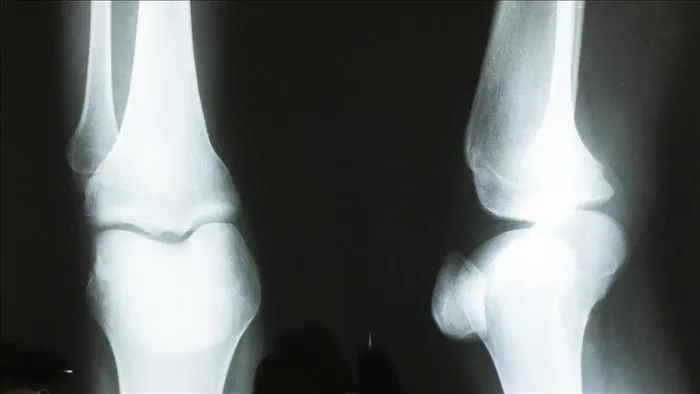

Osteoporoz yani kemik erimesi, en sık kırık nedenlerinden birini oluşturuyor. Kadınlarda bu hastalığa bağlı kırıklar 45 yaşından, erkeklerde ise 75 yaşından sonra daha sık görülüyor. Özellikle omurga, kalça ve el bileği kırıkları artıyor. Hayatı çekilmez kılıyor. İç Hastalıkları Uzmanı Prof. Dr. Osman Erk, osteoporozla ilgili önemli bilgileri TAKVİM'e anlatıyor: